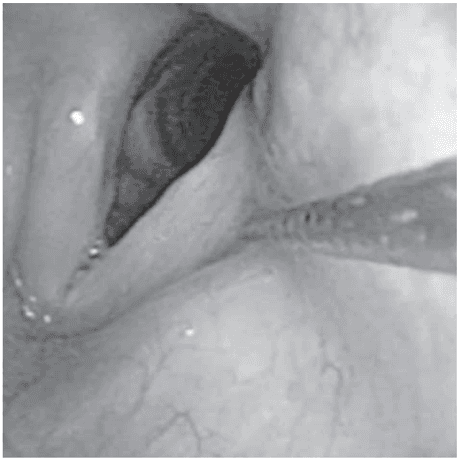

Transnasal endoscopic microfractured fat injection in glottic insufficiency

A. M. Saibene, C. Pipolo, R. Lorusso, S. M. Portaleone, G. Felisati, B-ENT, 2015